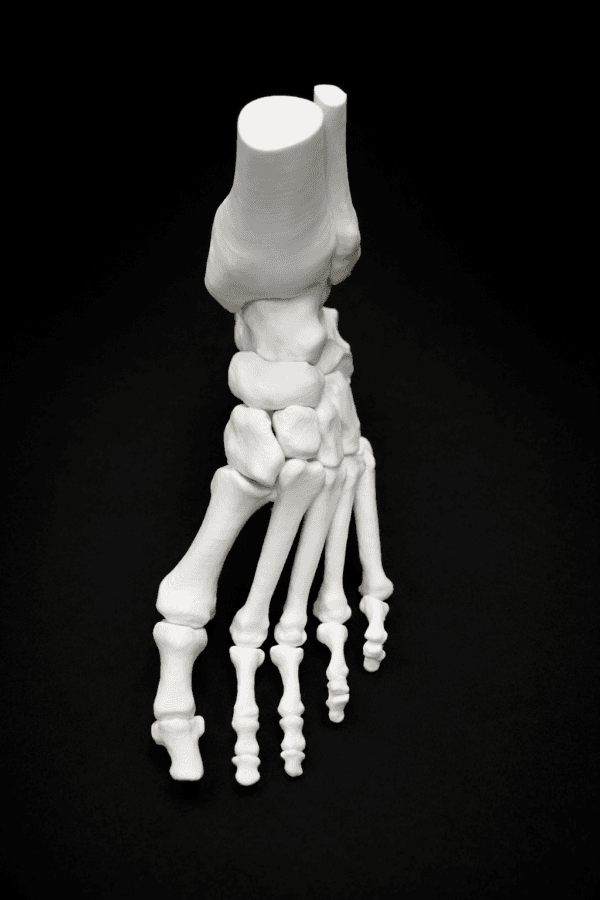

| Pathology | Pes Cavus |

| Procedure | Cole Osteotomy, Dwyer, Lateralizing Calcaneal Osteotomy, Metatarsal Dorsiflexion Osteotomy |

| Area | Midfoot |

| Modularity | Single-piece |

| Material | Opaque |

Pes Cavus – Bone Model